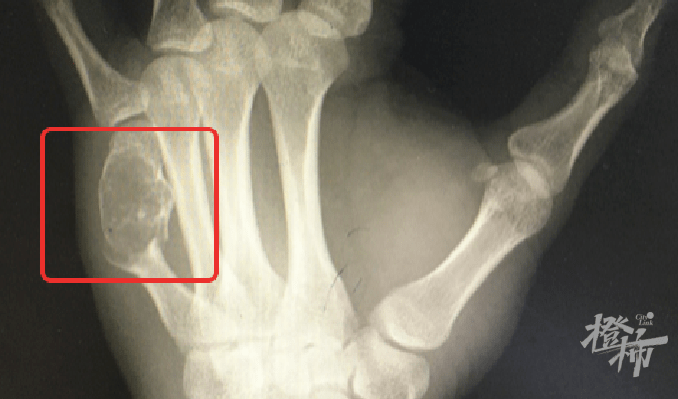

”这可不是一般的键盘手 , 你左手这根骨头里的东西 , 其实是内生性软骨瘤 , 它把你正常的骨头都‘融’成‘豆腐渣’了 , 所以骨头才会一碰就裂开 , 需要刮除肿瘤组织同时固定骨折的掌骨 。 ” 骨科马伟副主任医师指着X片对黄先生解释道 。

虽然普通X线检查往往就能明确诊断 , 但因为内生性软骨瘤一般没有症状或伴有轻微酸痛、无痛性肿胀 , 看起来更像肢体的局部肿胀 , 并且其生长速度缓慢 , 数年内体积也无明显变化 , 所以多数病人是出现了病理性骨折后才被检查出此病 。 而软骨肉瘤常常表现为局部肢体的疼痛 , 夜间疼痛可加重 , 并且其生长速度相对较快 , 摸起来凹凸不平 , 局部皮肤可能发红发热 , 甚至可以看到静脉血管怒张 。